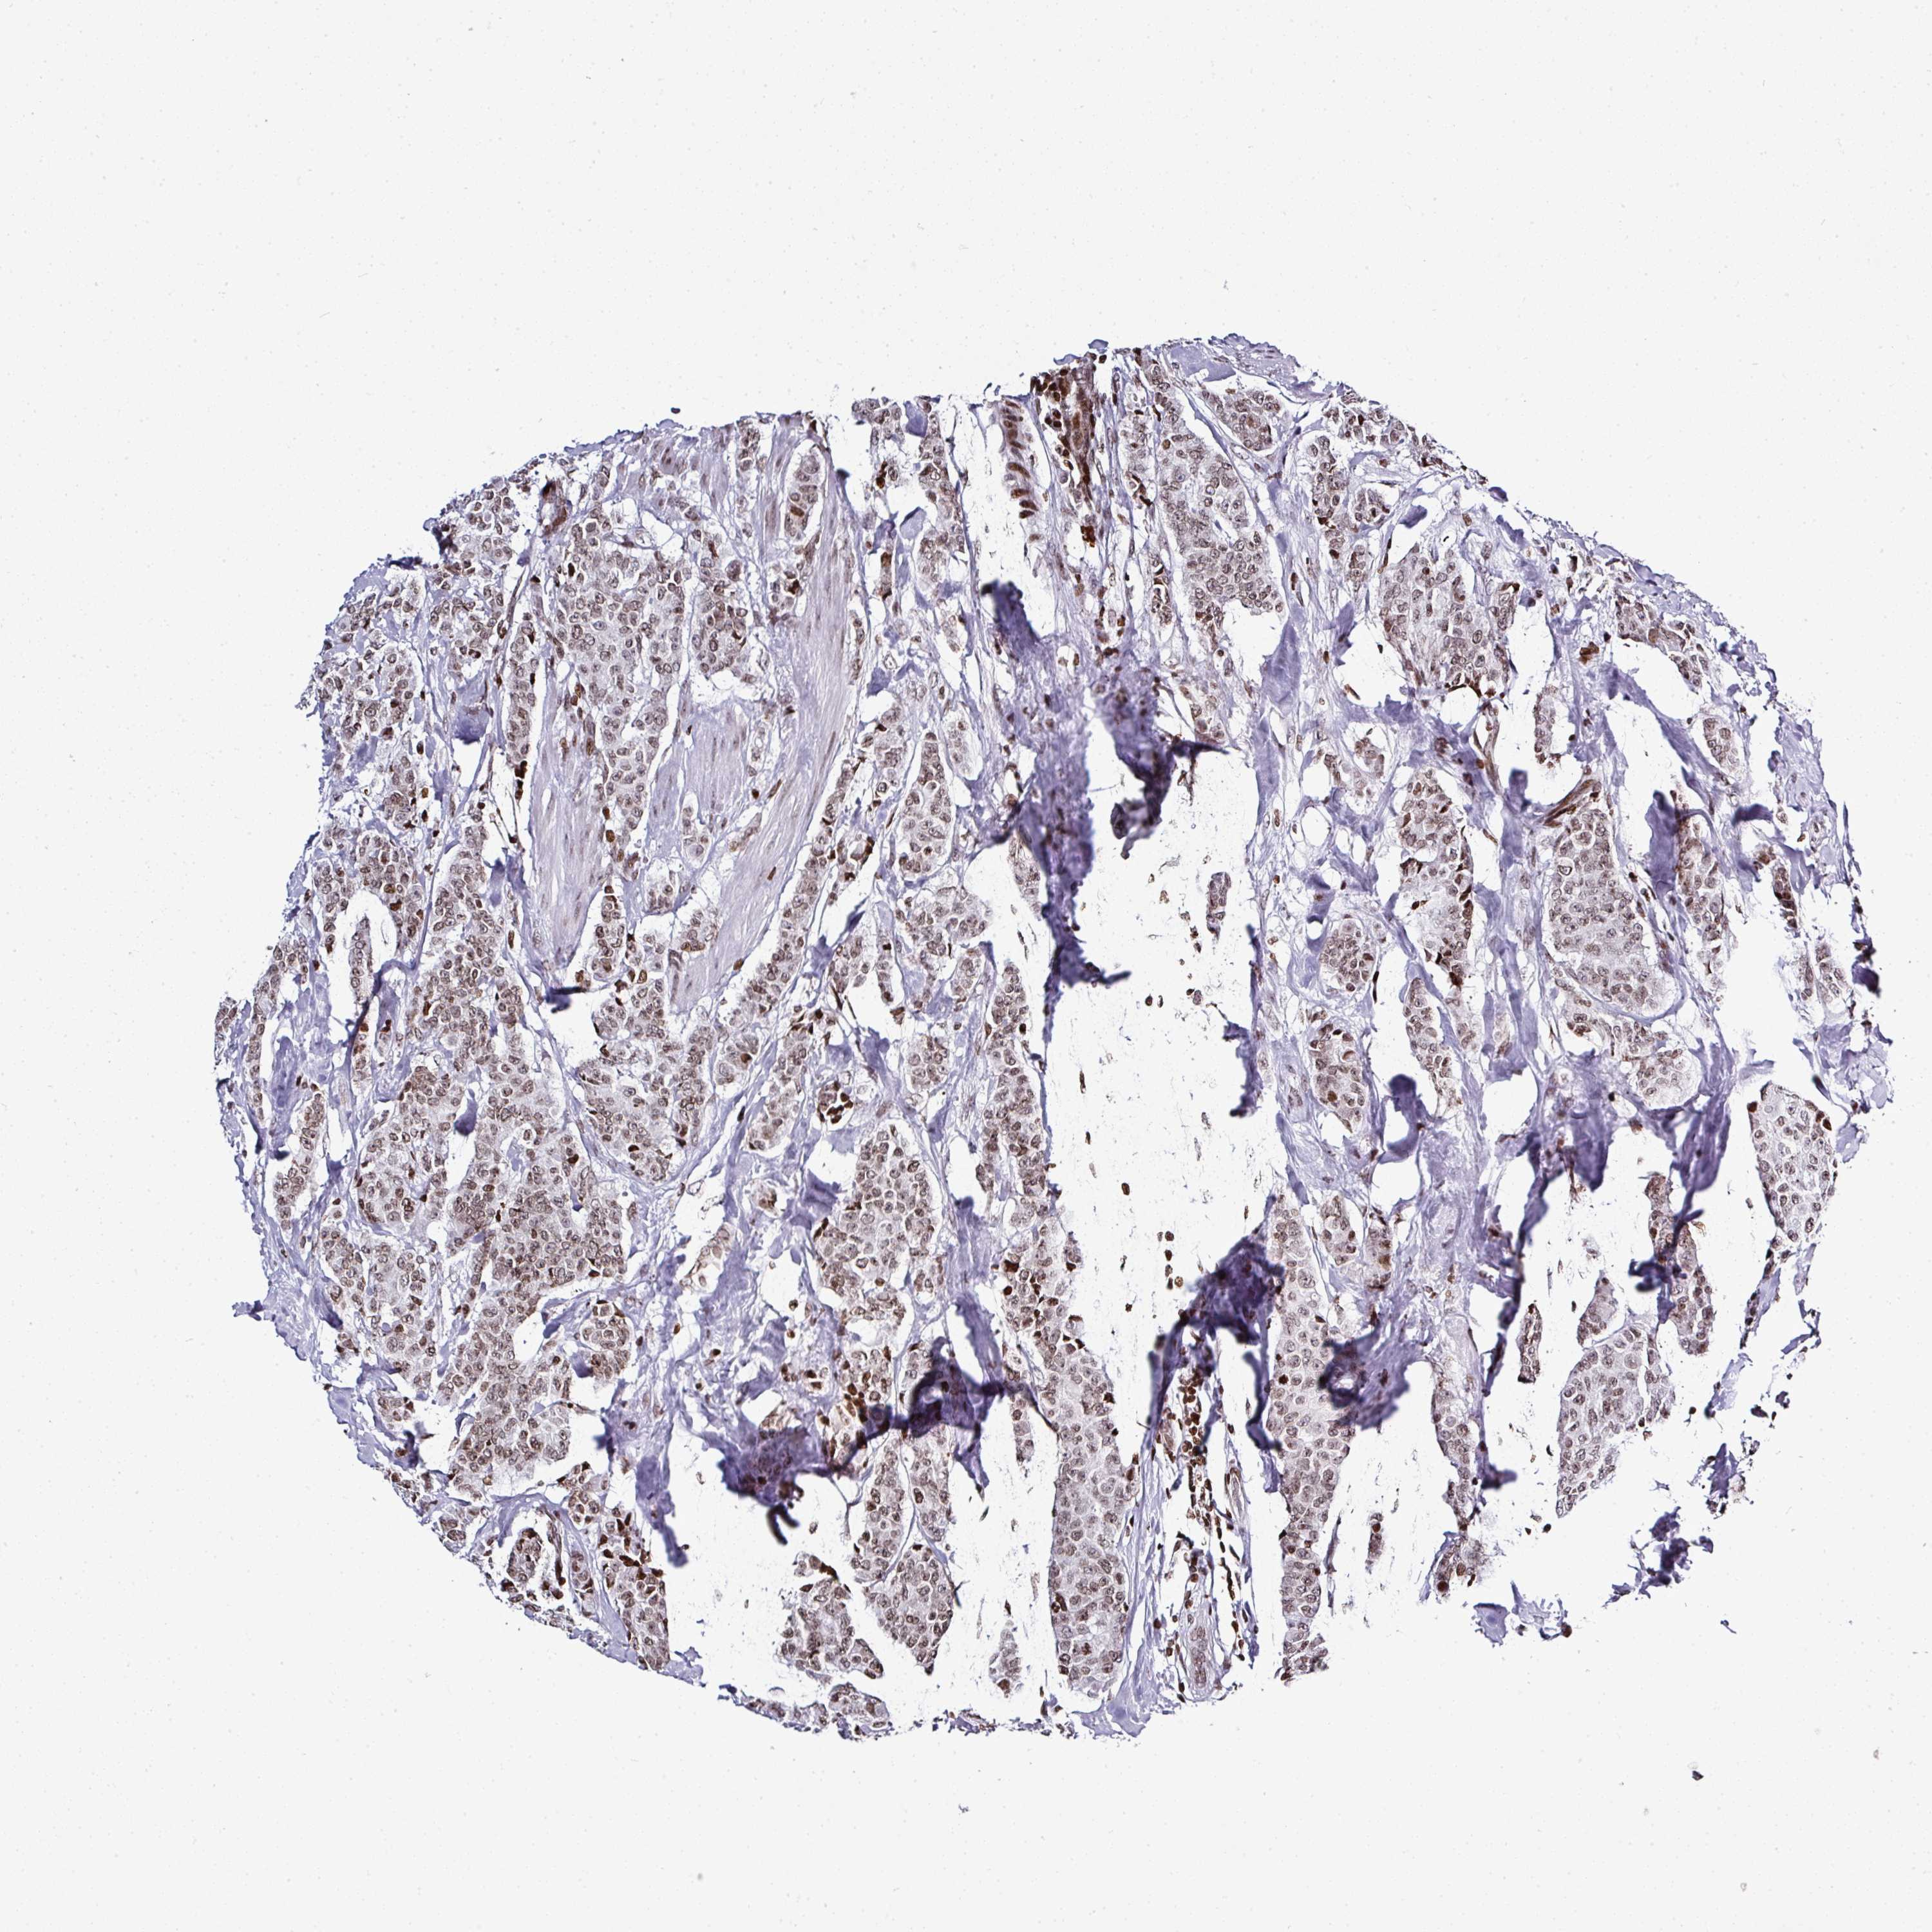

CANCER BREAST CANCER Show tissue menu

BRCA TCGA BRCA VALIDATION PROTEIN EXPRESSION

Breast cancer

Human cancer

Breast invasive carcinoma